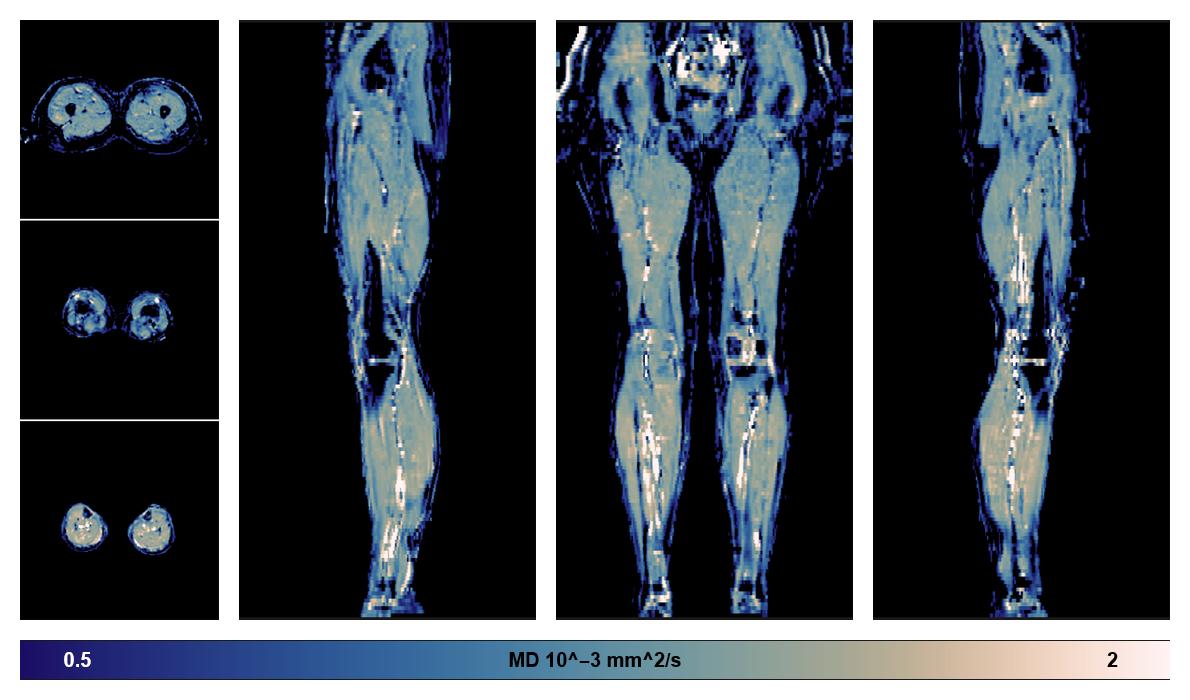

• Mean diffusivity

IVIM corrected whole leg muscle mean diffusivity obtained from diffusion tensor imaging.